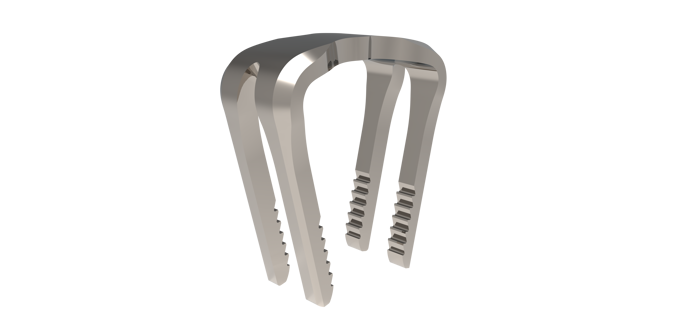

COGNiTiON™ Staple System

COGNiTiON™ STAPLE SYSTEM The staple that redefines strength and stability.